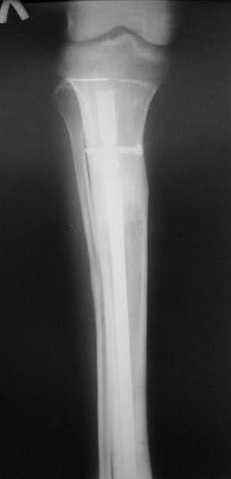

Пациент 19 лет, производственная травма, придавлен тяжелой плитой. Политравма (ISS 21).

1 - рентгенограмма (прошу прощения за качество) при поступлении;

Произведено ПХО, acute shortening (5 см), фиксация стержневым аппаратом Hoffman.

3,4 - через 4 недели наложен спице-стержневой аппарат, произведена остеотомия большеберцовой кости в верхней трети, раны зажили, проводилась дистракция в аппарате.